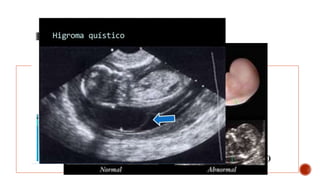

•Higroma quístico

SOSPECHA PRENATAL

-Hallazgos ultrasonográficos-

•Hidropesía fetal. •Aumento enla translucencia nucal •Higroma quístico •Polihidramnios •Retardo en el crecimiento intrauterino SOSPECHA PRENATAL -Hallazgos ultrasonográficos-